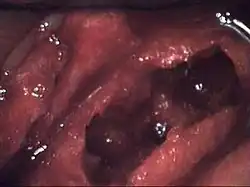

| Osteonecrosis of the jaw of the upper left jaw in a patient diagnosed with chronic venous insufficiency | |